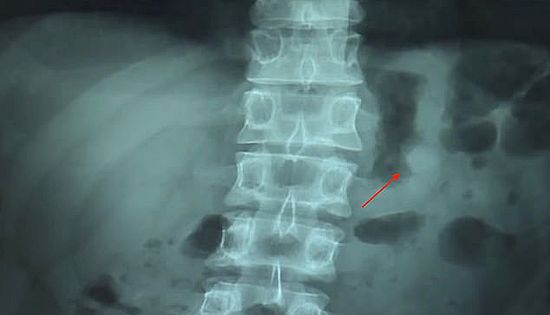

Никакого дискомфорта бедолага при этом не чувствовал, но на всякий случай пошел в больницу. Рентген подтвердил, что наушник "путешествует" по желудку.